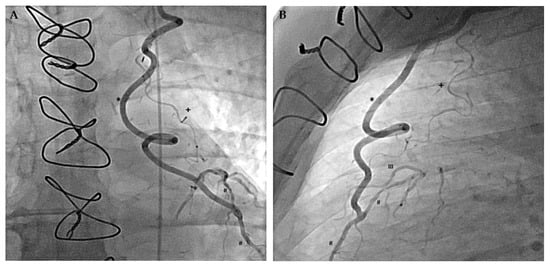

- Stoller, M.; de Marchi, S.F.; Seiler, C. Function of natural internal mammary-to-coronary artery bypasses and its effect on myocardial ischemia. Circulation 2014, 129, 2645–2652. [Google Scholar] [CrossRef]

- Stoller, M.; Seiler, C. Effect of Permanent Right Internal Mammary Artery Closure on Coronary Collateral Function and Myocardial Ischemia. Circ. Cardiovasc. Interv. 2017, 10, e004990. [Google Scholar] [CrossRef]